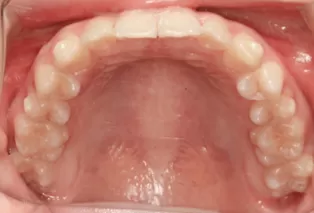

Photos intra-orales